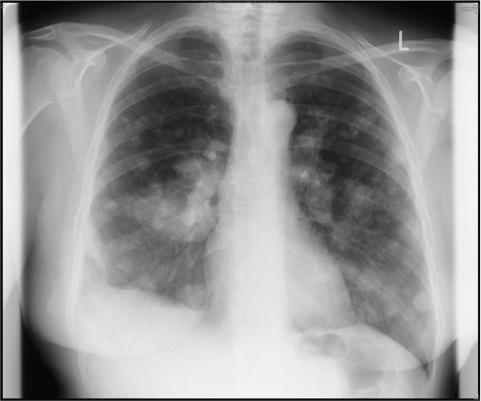

我要发布信息 | | 科学家发明新技术 让X光检查更安全 | 2015/02/17 |  | 腾讯科学讯 据国外媒体报道,当看见X光的时候,很多人都会联想起X光胸透检查以及它带来的各种危害。但现在你不用再害怕了,因为科学家通过先进的技术重组穿过不透明物体的光线,获得安全可见的X光透视。科学家通过调整空间光调制器中的激光,延迟它们的照射,以此同时,检波器计算出它们的轨迹,从而勾画出实体的透视画面。 去年,另一支在英国的科学家队伍将这种新技术应用在老鼠实验上,将老鼠的耳朵进行透视,实验很成功。这意味着,一种全新的全身透视设备将会诞生。事实上,这种技术不仅仅应用在医疗领域,还可以是考古、艺术甚至大众日常生活。有人建议该科学团队创建一个手机应用,让人们利用这种新技术看到世界上任何物体的透视画面,但该团队拒绝了这种想法。 |